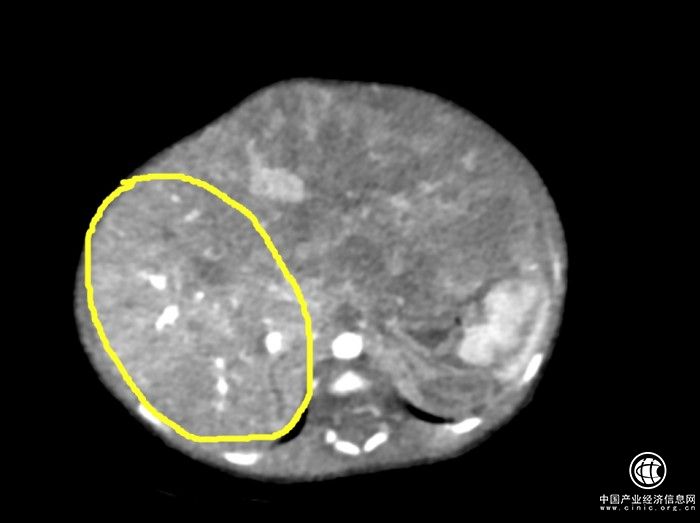

被肿瘤极度挤压的肝脏

经过多学科会诊,结论是孩子的肝母细胞瘤非常大,正常肝脏被极度挤压,随时有破裂可能,需要尽快手术。